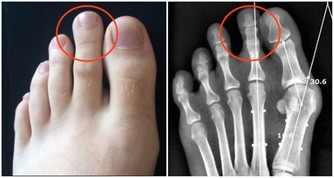

2. 骨盆疼痛

伴隨著不正常的出血,你還可能出現盆腔疼痛。疼痛可能是瀰漫性的,也可能是劇烈的疼痛或鈍痛,可以出現在骨盆的任何部位。如果近期出現新的骨盆疼痛,或與月經週期無關,最好看醫生。另外,性交或排尿期間疼痛也是警告信號。